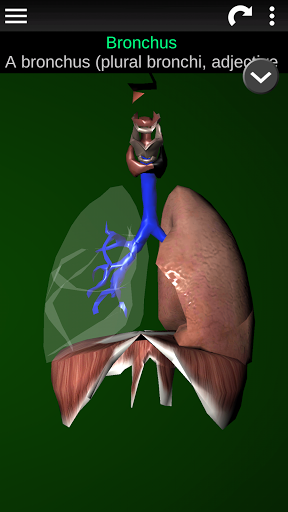

* Ademhalingssysteem, inclusief de luchtpijp, bronchiën, longen en een animatie van dit systeem.

* Gemakkelijk te openen en te navigeren (zoom, 3D-rotatie).

* Beschrijvingen van elk orgel.

Deze app is ontworpen als aanvulling op de studie van anatomie in verschillende onderwijs-, gezondheidszorg- en culturele omgevingen.